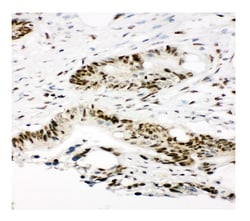

Reconstitute with 0.2 mL of distilled water to yield a concentration of 500 μg/mL. Positive Control - WB: human Hela whole cell, human A549 whole cell, human 293T whole cell, human HepG2 whole cell. IHC: human intestinal cancer tissue, human lung cancer tissue, human mammary cancer tissue, human mammary cancer tissue. ICC/IF: A549 cell, Hela cell. Flow: SiHa cell. Store at -20°C for one year from date of receipt. After reconstitution, at 4°C for one month. It can also be aliquotted and stored frozen at -20°C for six months. Avoid repeated freeze-thaw cycles.

| Flow Cytometry, Immunohistochemistry, Immunohistochemistry (Paraffin), Western Blot, Immunocytochemistry | |